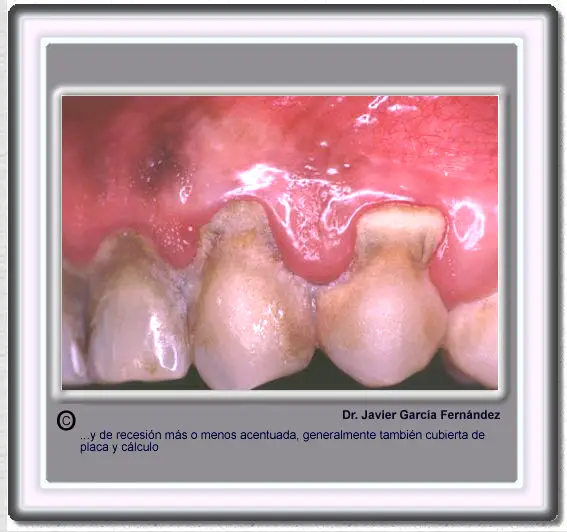

image310